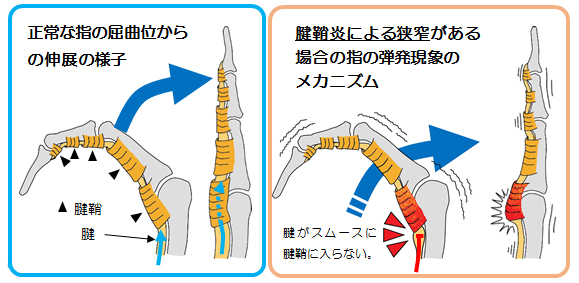

▶ 病態

指を曲げる屈筋腱は腱鞘というトンネルのような筒の中を通り、骨の近くを滑走できるようになっています。そのため特に指の付け根の掌側で擦れやすく、炎症が生じます。その結果、腱鞘の内腔が狭くなり、腱が肥厚することで、腱の通過障害が生じることが症状の原因です。通過障害が生じる原因は未だ不明ですが、手根管症候群と同様に女性ホルモンが関係している可能性があります。